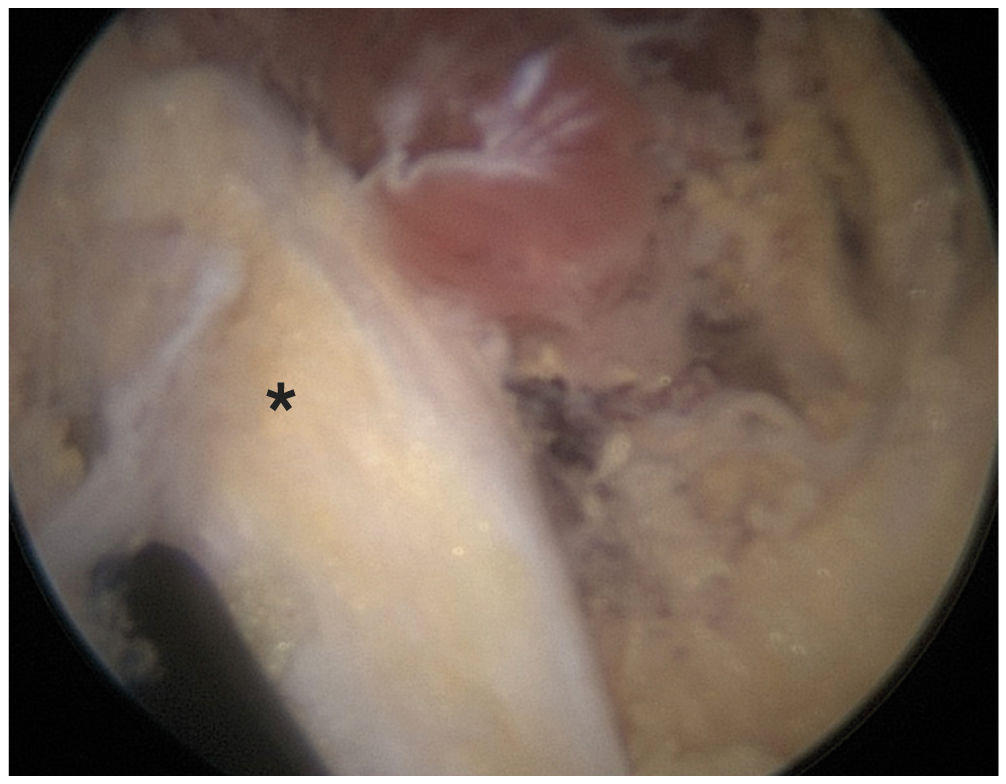

Пациентка госпитализирована в стационар для проведения хирургического вмешательства. Прооперирована в положении на животе под общим наркозом по опубликованной ранее эндоскопической методике [6, 10]. Операция выполнена эндоскопически с нагнетанием физиологического раствора с помощью артроскопической помпы. Выполнена эндоскопическая диссекция тканей в области подгрушевидного отверстия, визуализирован седалищный нерв, окружённый рубцово-спаечной тканью. Выполнены рассечение рубцово-спаечных тканей и невролиз седалищного нерва (рис. 1).

Рис. 1. Седалищный нерв (*) после выполнения невролиза.

Fig. 1. Sciatic nerve (*) after neurolysis.